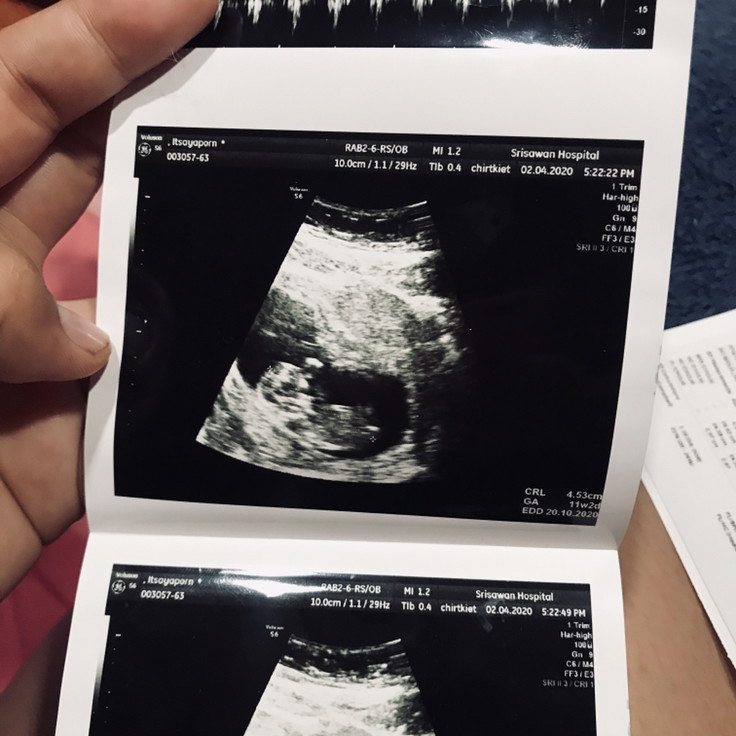

บ้านนี้ตอน11w ค่ะ

บ้านนี้ตอน11wค่ะ